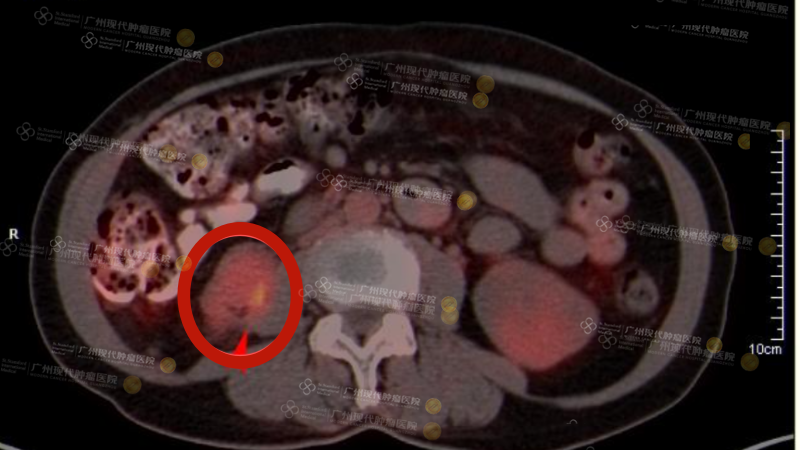

Hình ảnh CT trước điều trị: Sau phẫu thuật u mỡ vùng sau phúc mạc phải và cắt bỏ thận phải, tại vị trí thận phải trước đây ghi nhận một khối mô mềm dạng khối, kích thước khoảng 4,4 cm × 3,0 cm × 4,5 cm, với SUVmax = 5,6.